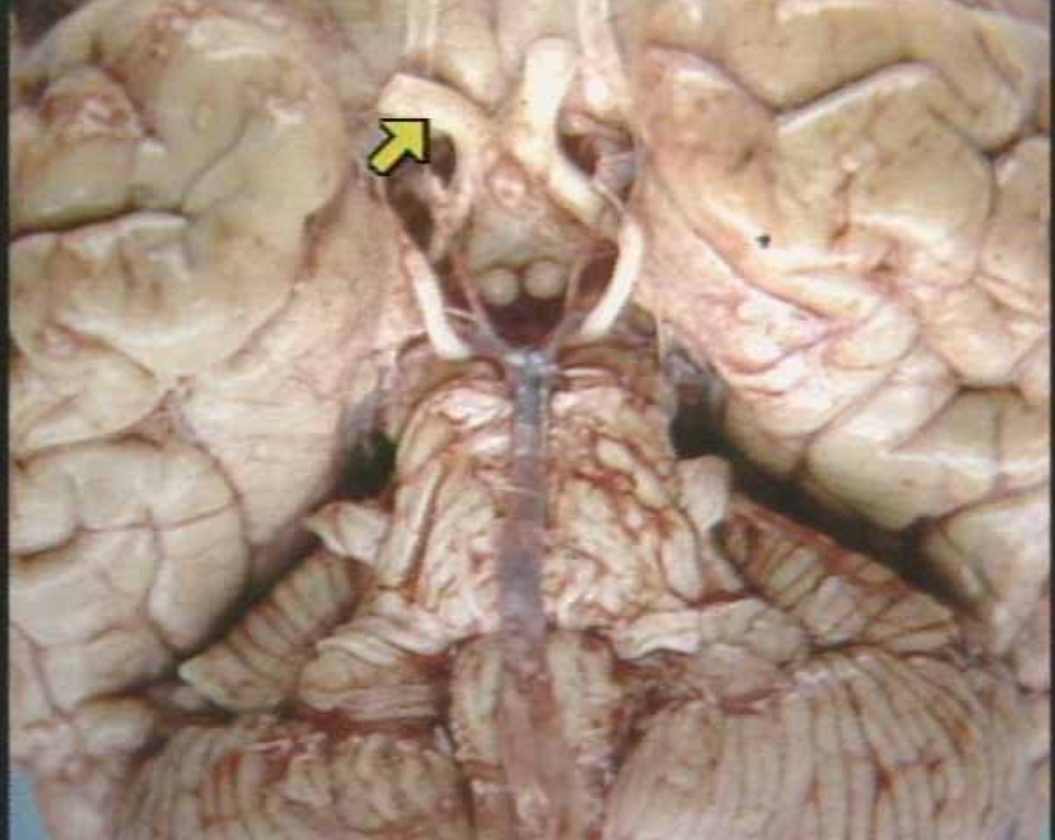

What is the arrow pointing at?

Amygdala

Basal Ganglia (Real Inferior View of Brain)